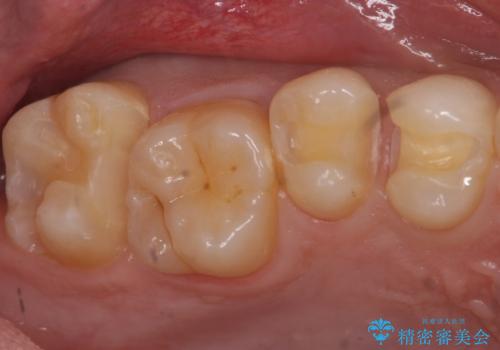

虫歯の除去後セラミックインレーでの修復処置をしていきます。

- 右上457 セラミックインレー 77,000円×3本費用は治療当時の料金となります

歯と歯の間は虫歯の好発部位とされています。

適合の良いインレーでの修復をすることで再発を防止します。